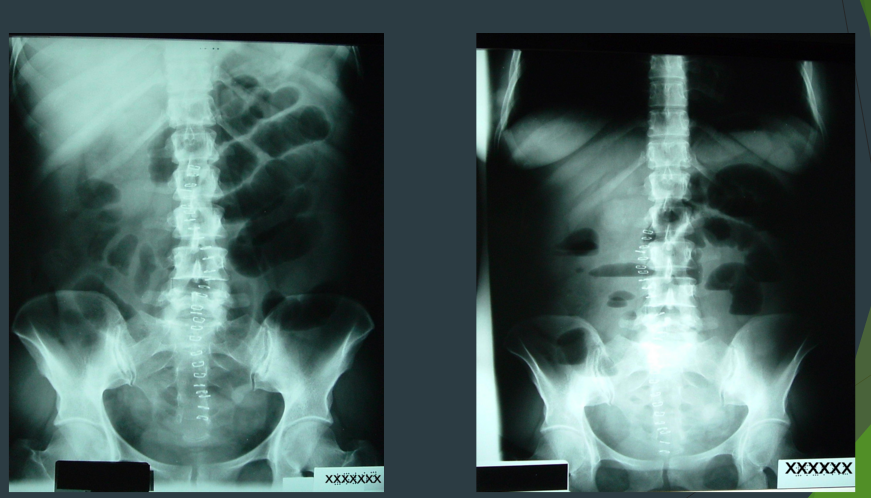

Ileus

After surgery

What are these xrays showing?

Constipation (full of stuff/stool)